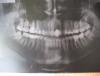

Павел_1 Опубликовано 16 мая, 2013 Автор Поделиться Опубликовано 16 мая, 2013 исправился.панорама - до установки имплантаодиночный снимок - после. Ссылка на комментарий

Mane Опубликовано 16 мая, 2013 Поделиться Опубликовано 16 мая, 2013 Снимки не настолько информативны чтоб сделать вывод о сложившейся ситуации. Сделайте КТ (компьютерная томография) Ссылка на комментарий

Павел_1 Опубликовано 16 мая, 2013 Автор Поделиться Опубликовано 16 мая, 2013 Снимки не настолько информативны чтоб сделать вывод о сложившейся ситуации.Сделайте КТ (компьютерная томография) я живу не в большом городе и сомневаюсь о наличии компьютерной томографии здесь да и времени уже нет. Но мне вот что интересно, выделение гноя по краям импланта и его подвижность - что это значит и что следует делать, с такими снимками какие есть? Ссылка на комментарий